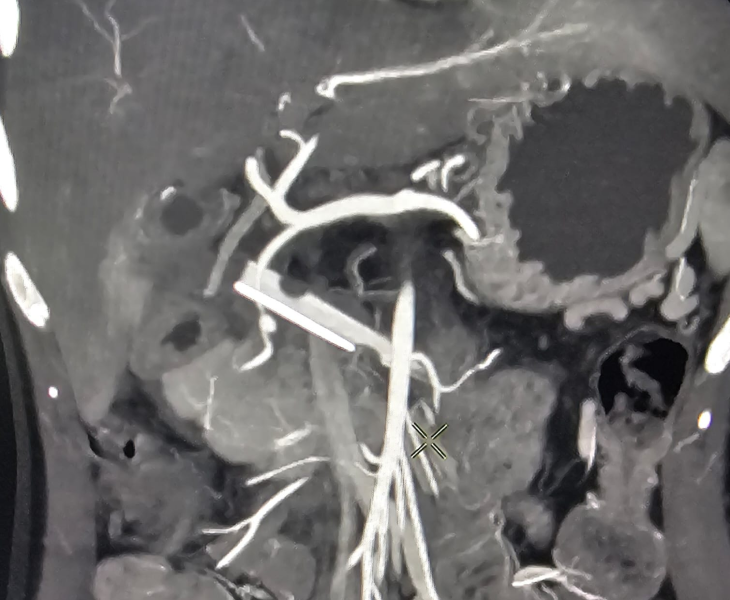

We use CT angiography and catheter angiography to identify the bleeding vessel precisely and then perform targeted embolization to seal it while preserving as much normal organ blood supply as possible.

- Catheter angiography: contrast is injected to locate the pseudoaneurysm and bleeding source.

- Super‑selective catheterisation: a microcatheter is advanced into the specific branch feeding the pseudoaneurysm.